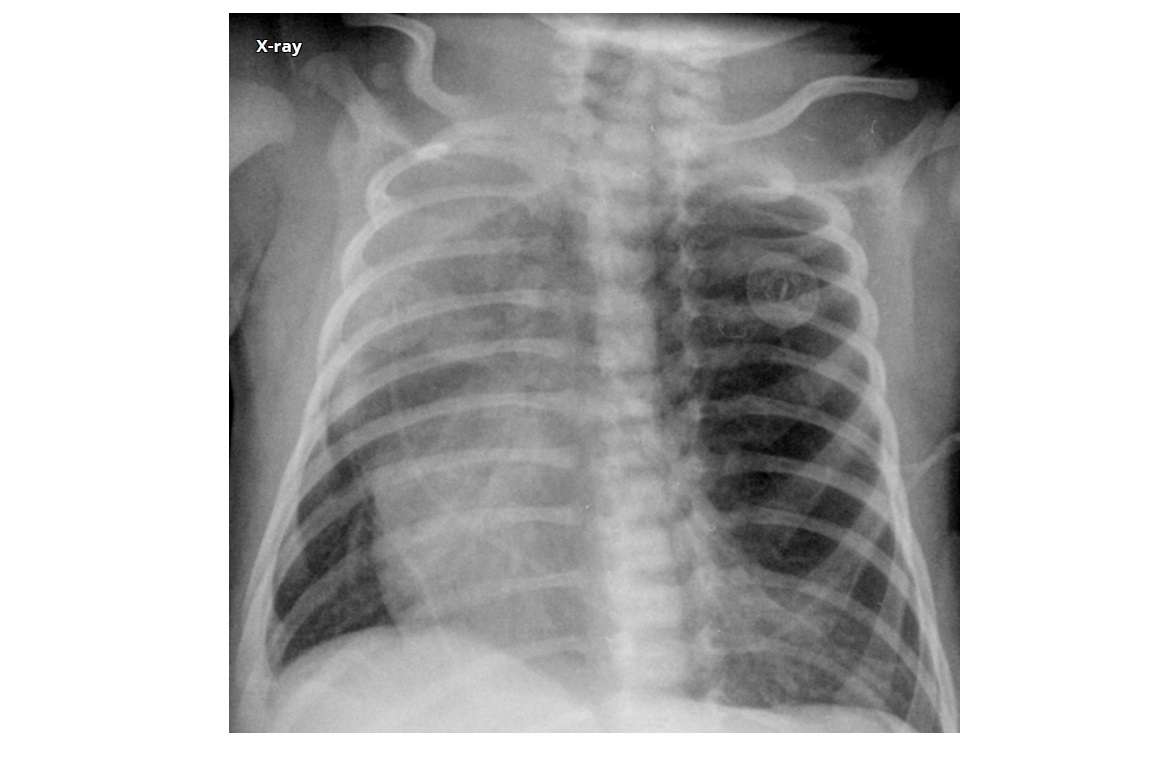

Round pneumonia

Young children

Pneumoccous, strep

Spherical area posterior lower lobes

With antibiotic and resolution of symptoms it doesnt need followed up